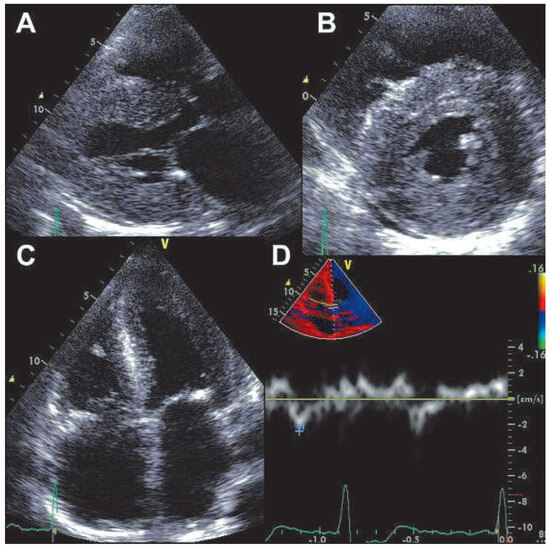

Prevalence and Pathology of Primary Cardiac Tumours

by Cristina Basso, Stefania Rizzo, Marialuisa Valente and Gaetano Thiene

Primary cardiac tumours are rare clinical observations, different from secondary neoplasms (ten times more frequent), and 90% of all primary cardiac tumours are benign. Myxoma is by far the most frequent benign tumour (75%), typically located in the left atrium, and manifests with [...] Read more.

Primary cardiac tumours are rare clinical observations, different from secondary neoplasms (ten times more frequent), and 90% of all primary cardiac tumours are benign. Myxoma is by far the most frequent benign tumour (75%), typically located in the left atrium, and manifests with intra-cavitary obstruction, embolism and constitutional symptoms, but it may also be silent and discovered incidentally by echo. Papillary fibroelastoma is a tumour usually arising on the valvular or mural endocardium, which, although quite small, may become symptomatic through embolic e vents. Typical tumours of the paediatric age group are fibroma, rhabdomyoma and teratoma. Primary malignant neoplasms account for 10% of all primary cardiac tumours and are represented by sarcomas (angiosarcoma, leiomyosarcoma, fibrosarcoma, liposarcoma, rhabdomyosarcoma undifferentiated pleomorphic sarcomas) and primary lymphomas. They usually infiltrate the cardiac walls, but may be also solely intra-cavitary, mimicking myxoma. Non neoplastic masses may consist of thrombi and infections, which again can be identified by a thorough surgical pathology examination. Cardiac non invasive imaging through transthoracic and transesophageal echocardiography easily detects heart masses. Cardiac magnetic resonance imaging a nd computed tomography are helpful complementary investigations, for refining diagnosis and in the post-surgery follow-up. Histology with immuno-histochemistry of any cardiac mass is mandatory for diagnosis, therapy and prognosis. Endomyocardial biopsy m ay be of help for histological investigation without thoracotomy particularly in right sided masses. Full article